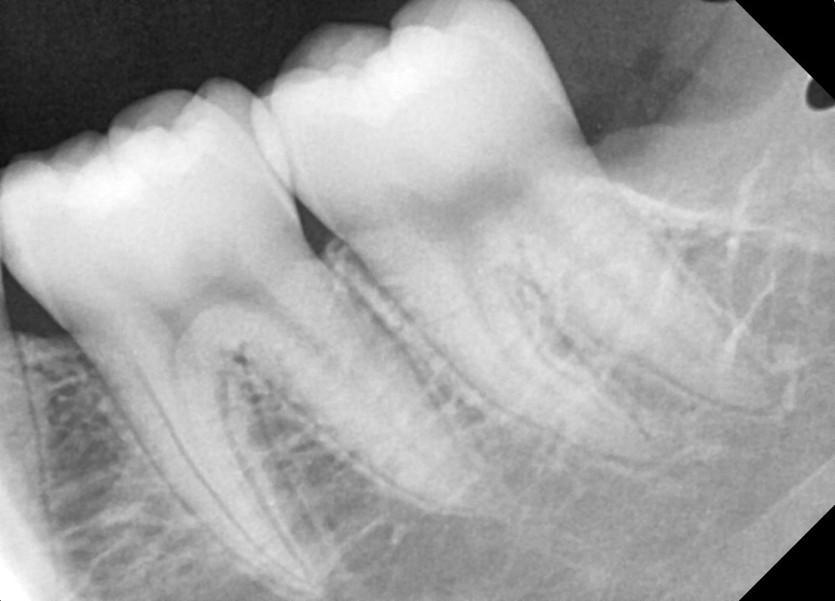

#28,38 사랑니 발치

구강 외과 전문의가 당일 발치했습니다.